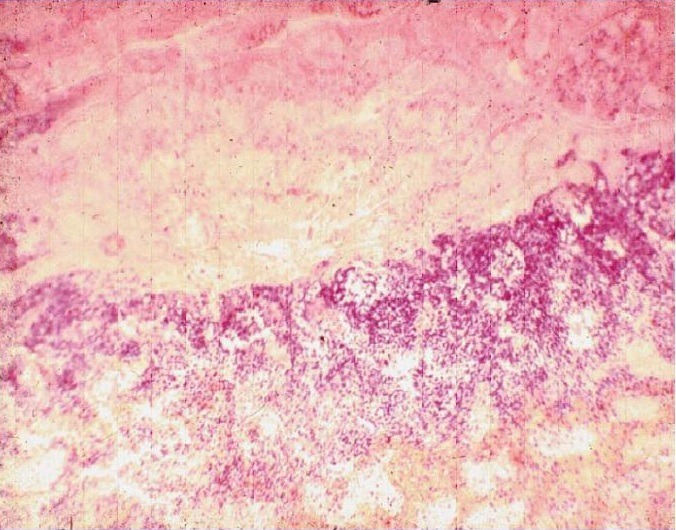

Ишемический инфаркт почки с демаркационной линией (гистологический препарат)